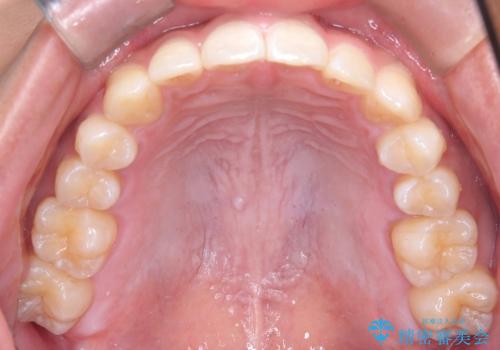

歯を抜かずに叢生(デコボコ歯列)と過蓋咬合を改善する事が出来ました。

インビザラインによる治療でも十分に美しい歯並びを実現でき、患者様にも大変ご満足いただけました。